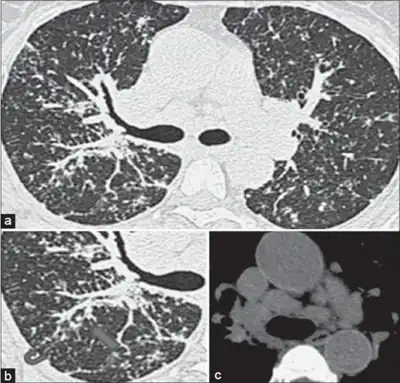

Definitive diagnosis of berylliosis is based on history of beryllium exposures, documented beryllium sensitivity and granulomatous inflammation on lung biopsy. Given the invasive nature of a lung biopsy, diagnosis can also be based on clinical history consistent with berylliosis, abnormal chest x-ray or CT scan findings, and abnormalities in pulmonary function tests.[14]

Chest radiography findings of berylliosis are non-specific. Early in the disease radiography findings are usually normal. In later stages interstitial fibrosis, pleural irregularities, hilar lymphadenopathy and ground-glass opacities have been reported.[16][17] Findings on CT are also not specific to berylliosis. Findings that are common in CT scans of people with berylliosis include parenchymal nodules in early stages. One study found that ground-glass opacities were more commonly seen on CT scan in berylliosis than in sarcoidosis. In later stages hilar lymphadenopathy, interstitial pulmonary fibrosis and pleural thickening.[17]